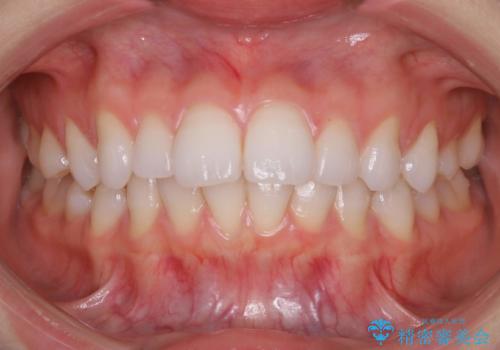

インビザラインで出っ歯を改善する 抜歯をしないinvisalign治療

- 非抜歯・遠心移動による前突の改善をマウスピースにて計画した。

非抜歯矯正の場合、大きく前歯を下げることはできませんが、奥歯の遠心移動や歯のサイズダウンにより歯軸を立て、見かけ上の出っ歯感をある程度改善することができます。